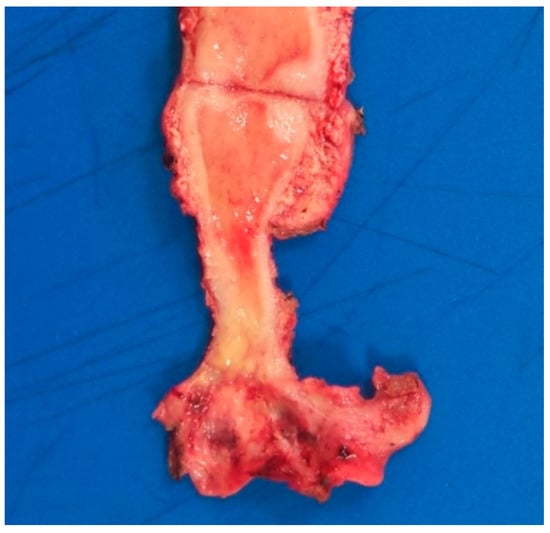

2. Case Report